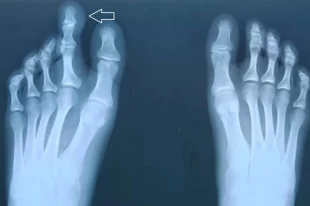

Медики из Владимира укоротили палец 17-летней пациентке

У девушки редкое заболевание.